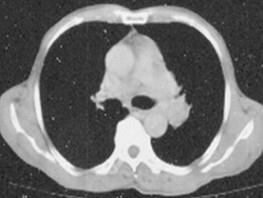

问题 60岁,男,有长期抽烟史,左声带麻痹、声音嘶哑2个月,请结合胸片和CT图.选出最可能的诊断 ( )

选项 A、肺炎 B、肺结节病 C、肺结核 D、尘肺 E、肺癌

答案 E